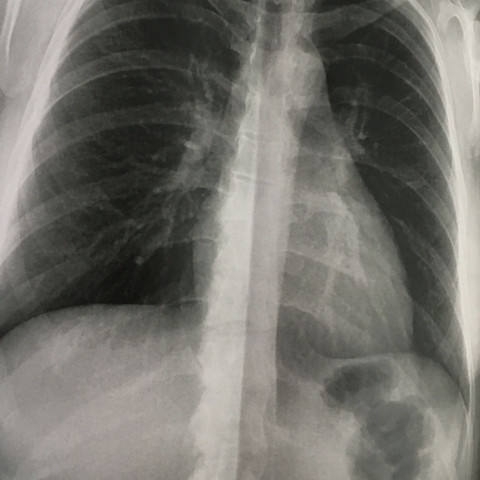

Brustkorb

Thoraxtrauma Wikipedia